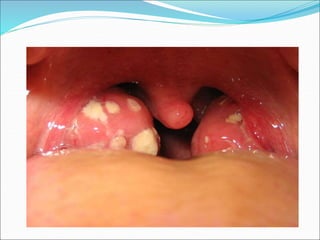

Tonsillitis

Mostly Viral as part of URTI

5-30% caused by bacteria

 Grp A β haemolytic strep (most common)

 H.influenzae

 Staph aureus

 Strep Pneumoniae

Management

 IV antibiotics – benzyl-pen +/- metronidazole

 IV fluids

 Adequate analgesia

Tonsillitis Mostly Viral aspart of URTI 5-30% caused by bacteria  Grp A β haemolytic strep (most common)  H.influenzae  Staph aureus  Strep Pneumoniae Management  IV antibiotics – benzyl-pen +/- metronidazole  IV fluids  Adequate analgesia